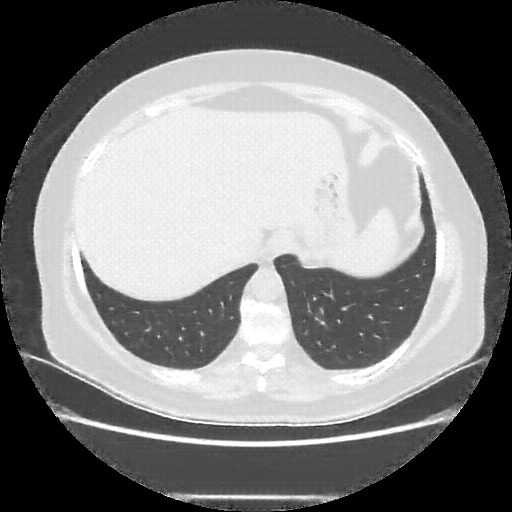

Generated VENOUS CT scan (A→B translation)

Full window (WL 1023.5, WW 4095 β†’ Low βˆ’1024, High +3071)

Actual HU range: [-1024.0, 864.1]